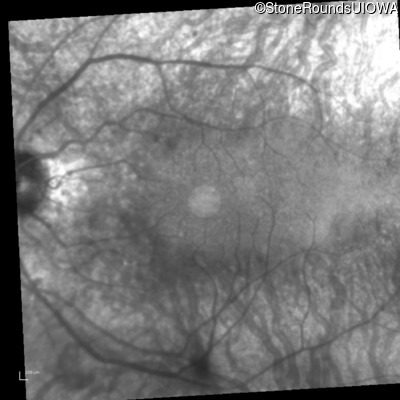

Infrared Fundus Photograph - Right - 20/32

Exemplar